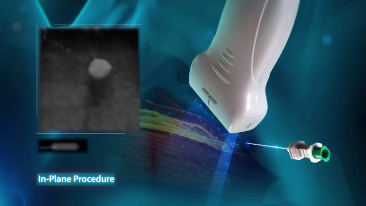

Sinds de oprichting van het bedrijf is Mindray voortdurend op zoek naar nieuwe manieren om het diagnostisch vertrouwen te vergroten. Resona 7 wordt aangestuurd door de meest revolutionaire ZONE Sonography?-technologie. Zijn nieuwe ZST+-tilt de kwaliteit van ultrasoundbeeldvorming naar een hoger niveau door middel van zoneacquisitie en kanaalgegevensverwerking.

Naast de hoogwaardige beeldvormingskwaliteit verbetert de Resona 7 tevens de klinische onderzoeksmogelijkheden met de revolutionaire V Flow voor vasculaire hemodynamische evaluatie, en de intelligentste vlakacquisitie van een 3D-gegevenssets voor de diagnose van het foetale, centrale zenuwstelsel. Met zijn combinatie van de meest intu?tieve, op vingerbewegingen gebaseerde multi-aanrakingsbediening en alle essenti?le klinische functies loopt de Resona 7 voorop in de nieuwe golven van ultrasoundinnovatie.